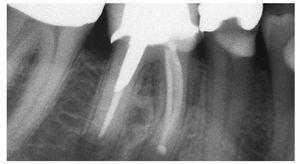

Calidad de la imagen: gracias a los sistemas digitales se ha podido seguir reduciendo el grosor de corte, lo que ha permitido mejorar notablemente la calidad de imagen especialmente en el sector posteroinferior (fig. 1).

Figura 1. Control postoperatorio después de la colocación de un implante en la mandíbula derecha.